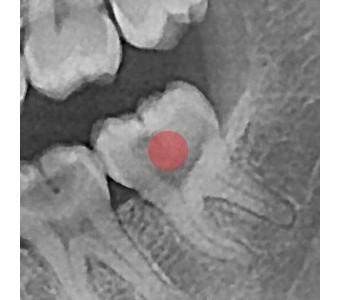

以成果证明实力。

国际摩牙齿科

真实临床案例